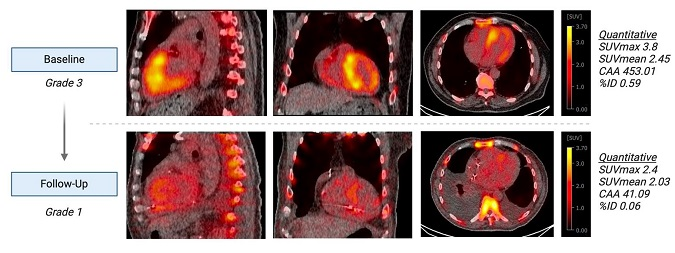

A tracer kinetic model can enable quantitative measurement of cardiac amyloidosis burden and assessment of treatment response, according to a study presented at the annual Society of Nuclear Medicine and Molecular Imaging (SNMMI) meeting in Chicago.

After assessing a number of methods for quantifying F-18-flutemetamol myocardial uptake on PET exams in patients with transthyretin (ATTR) cardiac amyloidosis, researchers led by Qiong Liu, a doctoral student at Yale University in New Haven, CT, found that a two-tissue reversible compartment model produced the best results in patients with this rare, life-threatening disorder.

A two-tissue reversible compartment model was the winner. The simplified graphical Logan plot identified the volume of distribution parameter generated from the first 30-minute dynamic scan was a quantitative parameter deemed by the researchers to be potentially useful for diagnosing and evaluating treatment in patients with ATTR cardiac amyloidosis.